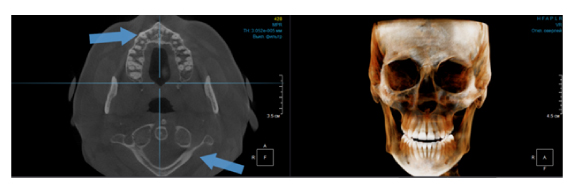

Когда мы отправляем пациента на проведение рентгенологического исследования, то подвергаем его определенному риску. Именно это нужно осознавать, так как в радиологии нет минимально безопасной дозы, поэтому любое назначение должно быть обоснованным. В связи с этим поле обзора является достаточно принципиальным параметром. Если вы врач-терапевт, занимающийся эндодонтией или ортопед, который решил оценить состояние зубов перед протезированием, то вы должны понимать, что проведение исследования с полем обзора 10x10 см будет гораздо информативнее нежели большие снимки (18x16 см и выше). В первую очередь это связано с размером вокселя, о нём я напишу чуть ниже, а второе это то, что вам придется увеличивать изображение по каждому корневому каналу, и от этого вы будете терять в качестве снимка (рис. 1). И ситуация наоборот, если вы ортодонт, то чтобы использовать весь диагностический потенциал, а также возможность загрузить данные для расчёта 3D цефалометрии, то вам нужны снимки, захватывающие весь лицевой отдел черепа. Таким образом, дентальный томограф должен обладать возможностью проведения исследований с разным FOV, обеспечивая нужды всех специалистов. Если ваша клиника базируется на терапевтическом, хирургическом и ортопедическом приёме, то на мой взгляд, можно рассмотреть дентальные томографы с полем обзора 10x10 см или 16x10 см. Последний больше актуален для тех, кто работает с ВНЧС, так как антропометрически в 16 см даже у брахицефалов сустав должен попадать. Если в клинике есть ортодонтическое направление, функциональная стоматология, ЛОР-практика или ЧЛХ, то, безусловно, вышепредставленные снимки не будут отражать всех данных, которые необходимы для диагностики и планирования лечения. Здесь лучше рассмотреть конусно-лучевые компьютерные томографы с зоной сканирования 18x16 или 20x20 см. Особо стоит отметить понятие «сшивки». Есть дентальные томографы, которые делают один цельный снимок размерами, которые описаны выше, а есть аппараты, которым нужно провести две экспозиции и сшить изображения вместе, чтобы получился необходимый объём исследования. Как правило, вторые томографы чуть дешевле, но всё зависит от того, насколько вам нужна максимальная точность исследования. Если при сшивке челюсти и зубы, как правило, совмещаются практически идеально, то на уровне позвоночного столба происходит наслоение тканей и от него уже не избавиться (рис. 2). Второй отрицательный момент – это износ оборудования, логично, что он будет быстрее, так что экономия средств — это ещё спорный вопрос.

Рис. 1. Представлены два исследования (10x10 см и 20x20 см). На обоих изображениях хорошо видна канально-корневая система зубов, но, если масштабировать второе исследование, то качество неминуемо снизится, как и диагностическая эндодонтическая эффективность.

Рис. 2. Левый снимок представлен исследованием 20x20 см единым изображением. Стрелками показаны чёткость канально-корневой системы зуба, а также позвоночника. Правый снимок представлен исследованием 16x15 см с функцией сшивки. Стрелками обозначены чёткость зуба, но двойной контур позвоночника.